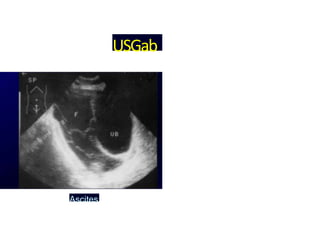

USGab

Ascites

domen

Right lower quadrant mass